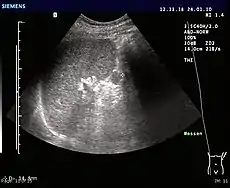

Ultrasonography of an accessory spleen. Ultrasonography of an accessory spleen.